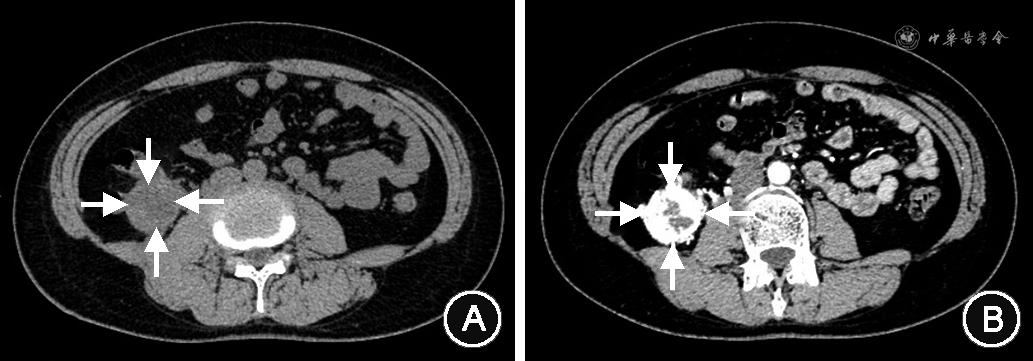

患者女,47岁,因“体检发现右肾占位4 d”于2018年3月2日入住吉林大学中日联谊医院。患者无腰痛,无血尿,一般状态可,基本生命体征正常,否认高血压、糖尿病、冠心病病史,无肿瘤家族史。入院后完善相关辅助检查,常规超声:右肾下极见一高回声团块,大小4.0 cm×3.3 cm,边界欠清晰,向肾外突出(图1A)。超声造影:肿物呈快进、慢退,周边见环状高增强,内部呈不均匀高增强(图1B)。超声提示:考虑肾恶性肿瘤。肾CT检查:平扫见右肾下极稍低密度团块影(图2A),增强扫描病灶呈明显不均匀强化(图2B),提示肾透明细胞癌。结合相关检查,临床诊断为右肾肿瘤,2018年3月13日在腹腔镜下行右肾根治性切除术。术后病理回报:右肾下极多彩样肿物一枚,间质见广泛出血、变性,提示透明细胞乳头状肾细胞癌(clear cell papillary renal cell carcinoma,CCPRCC),病理分期:Ta1,世界卫生组织/国际泌尿病理学会(WHO/ISUP)病理分级:Ⅱ级。免疫组化:细胞角蛋白7(CK7)(+),波形蛋白(Vimentin)(+),碳酸酐酶Ⅸ(CAIX)(+),高分子量角蛋白(34βE12)(+),配对盒基因8抗原(PAX-8)(弱+),细胞增殖核抗原Ki-67(1%+),白细胞分化抗原10(CD10)(-),α-甲酰基辅酶A消旋酶(P504S)(-)。患者术后随访36个月,未见复发及转移。